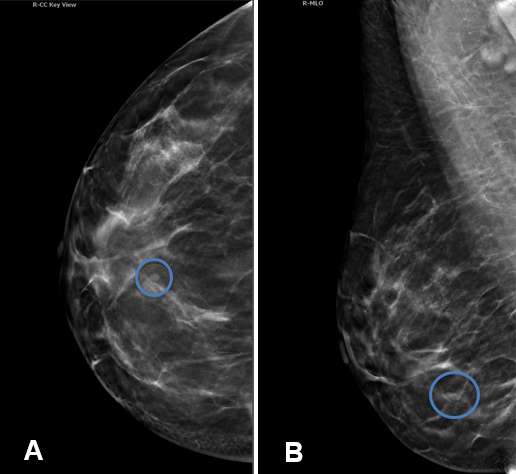

Simple breast cysts are benign, fluid-filled lesions that do not have malignant potential. Simple cysts have characteristic features on mammography and ultrasound that allow definitive diagnosis.

Mammography - Mammography often plays a complementary role in the assessment of simple breast cysts. They typically appear as well-circumscribed, oval or round, low density masses on mammogram. The density is often similar to that of surrounding fibroglandular tissue and background parenchymal elements are often discernible through the mass. Absence of associated microcalcifications and architectural distortion are additional reassuring features in differentiating a cyst from a solid mass.